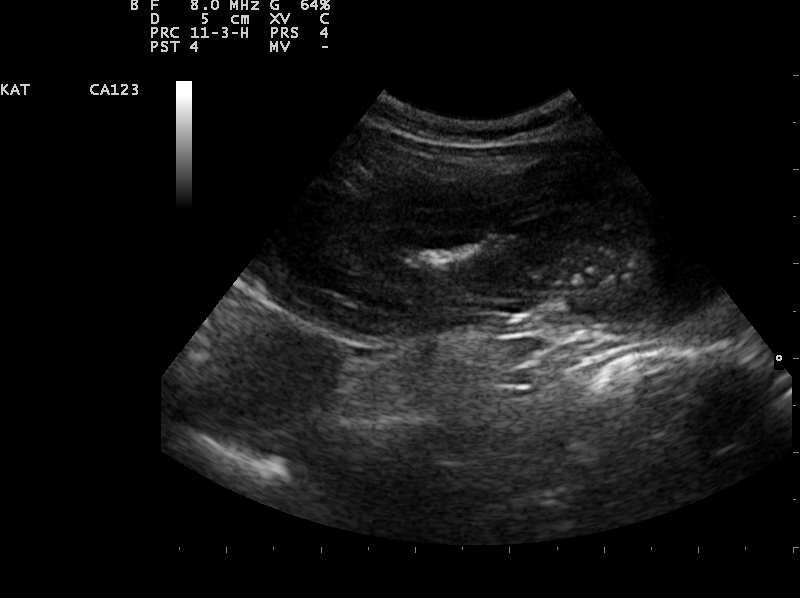

Een echo is het duidelijkst om een invaginatie te zien. Wanneer een invaginatie permanent is, zal deze met de echo meestal goed zichtbaar zijn. Echter wanneer het een temporel invaginatie is, kan dit heel lastig zijn. Een temporele invaginatie is een invaginatie die het ene moment er is en het andere moment niet. Deze invaginaties belemmeren meestal de passage maar sluiten het niet geheel af.

Een echo beeld van een darminvaginatie in lengtedoorsnede.